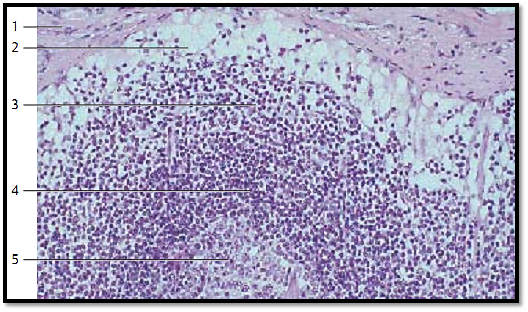

Outer region of a lymph node from the human axilla, with a relatively tough connective tissue capsule 1 , marginal sinus 2 and cortex 3. Reticulum cells (sinus reticulum ) and reticulum f ibers are clearly visible in the marginal sinus . They traverse the marginal sinus and form a loose meshwork . Note the sub capsular cells, name d mantle cells, which are similar to endothelial cells. Intermediary sinuses, which push through the compact cortical tissue, connect the marginal sinuses with the wide medullary sinuses. Lymphocytes are densely packed underneath the marginal sinus. They form a secondary follicle with a lymph corona 4 and a germinal center 5 .

1 Capsule

2 Marginal sinus

3 Cortex

4 Lymph corona of the secondary follicle

5 Germinal center

Stain: alum hematoxylin-eosin; magnification: × 200